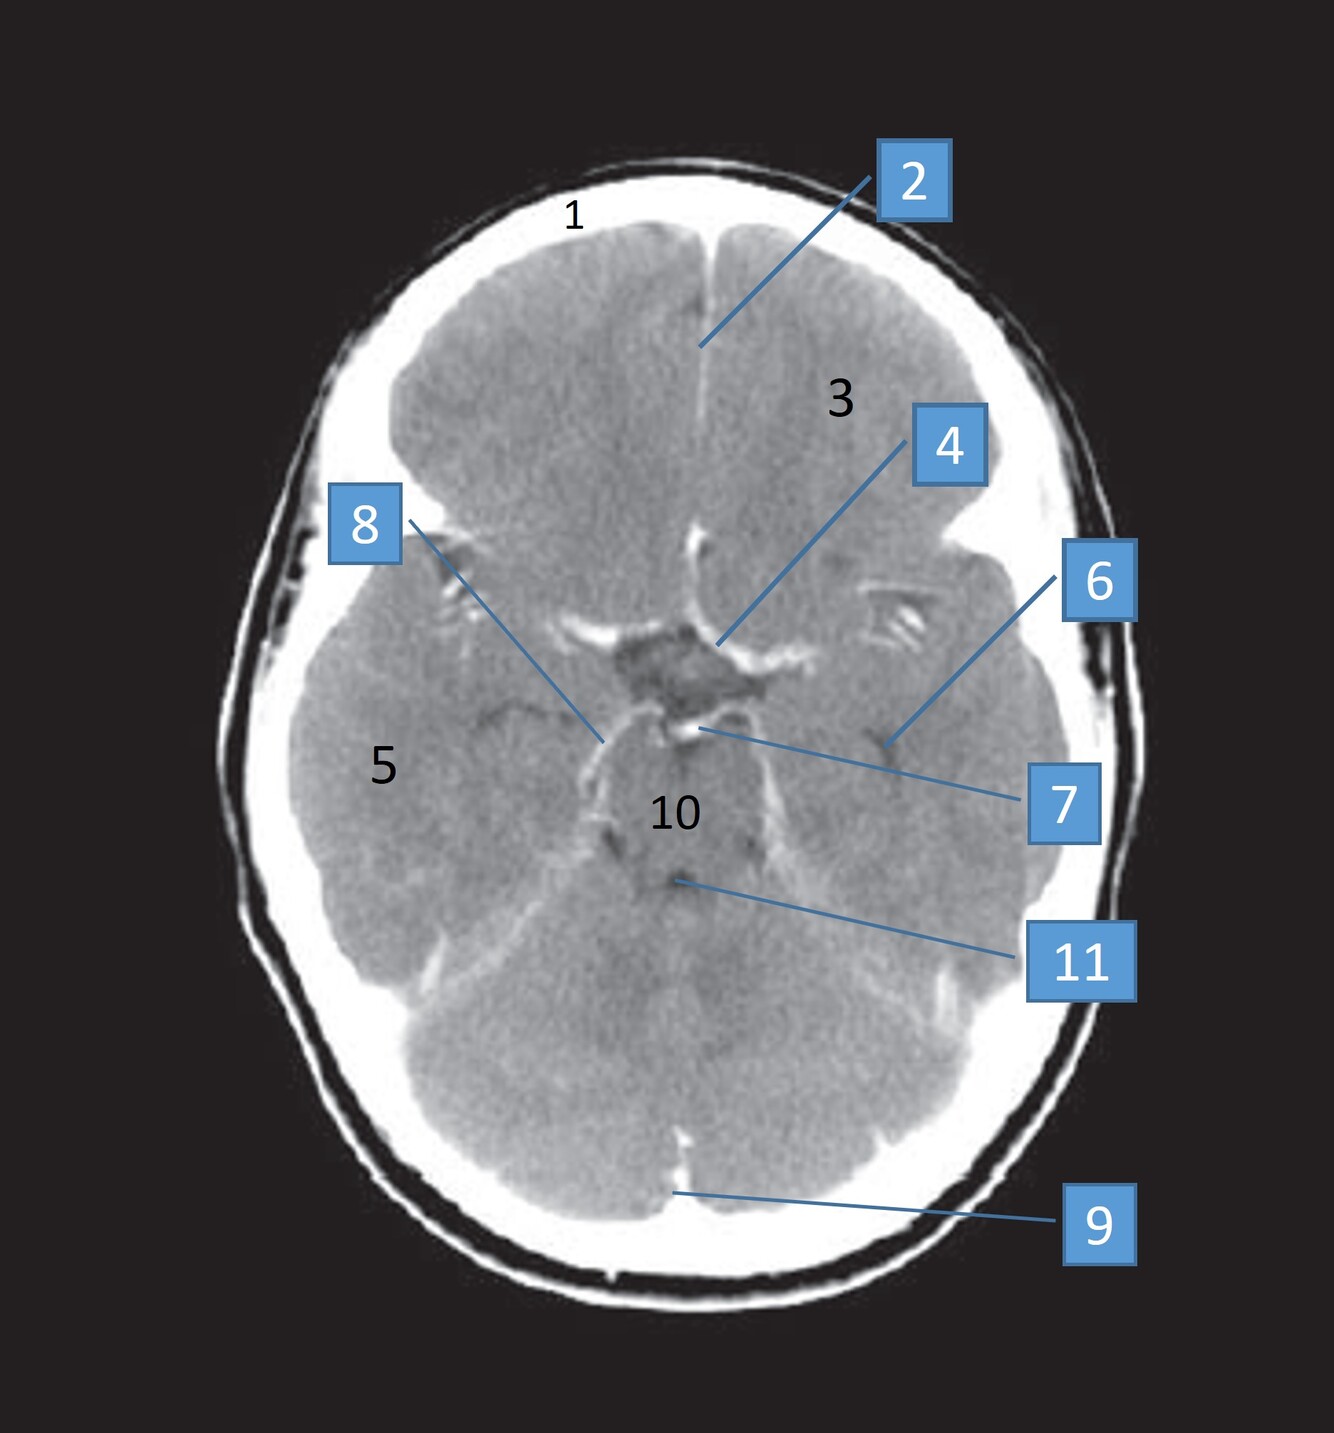

5

Label 2,3,4,5,7,8

A

2=Rt Caudate nucleus

3=Corpus callosum

4=Lt lateral ventricle

5=Third ventricle

7= Septum Pellucidum

8= Rt Interventricular foramen